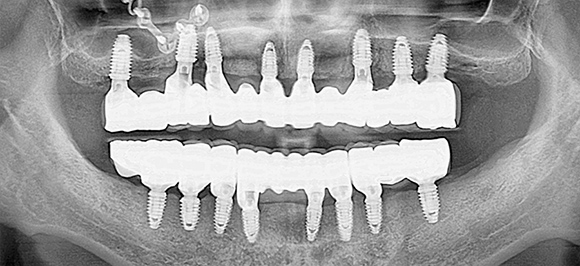

전악 임플란트 (풀케이스)

대부분의 치아를 상실했거나 발치를 해야 하는 경우

모든 치아에 임플란트를 식립하는 것이 아닌

주변까지 지지대 역할을 할 수 있는 임플란트 최소량만을 식립